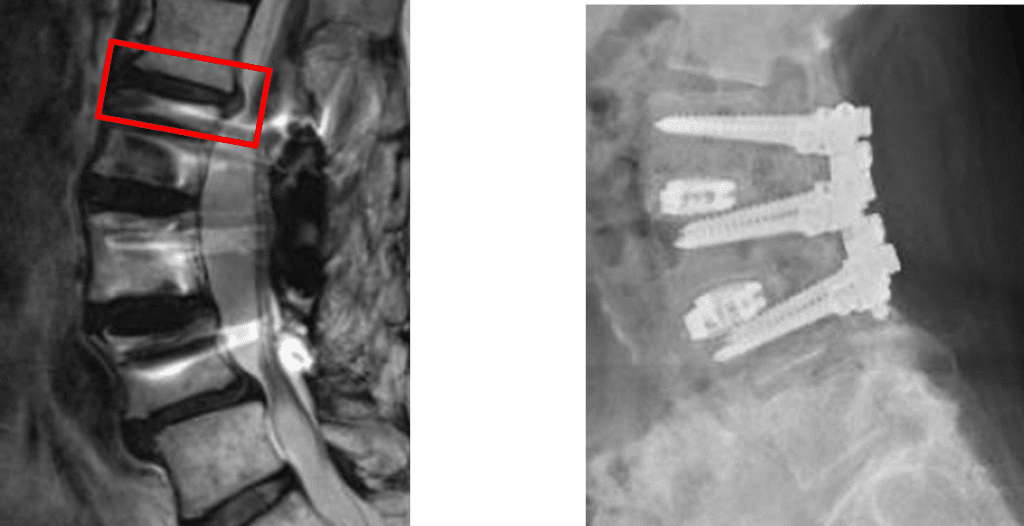

この患者様は赤い枠で示されている箇所(L1/2)にを椎間板ヘルニアを認めます。

L2/3,3/4に固定術をされています。

固定術後に新たにL1/2の椎間板ヘルニアが今回の主症状の可能性が高いと考えられます。